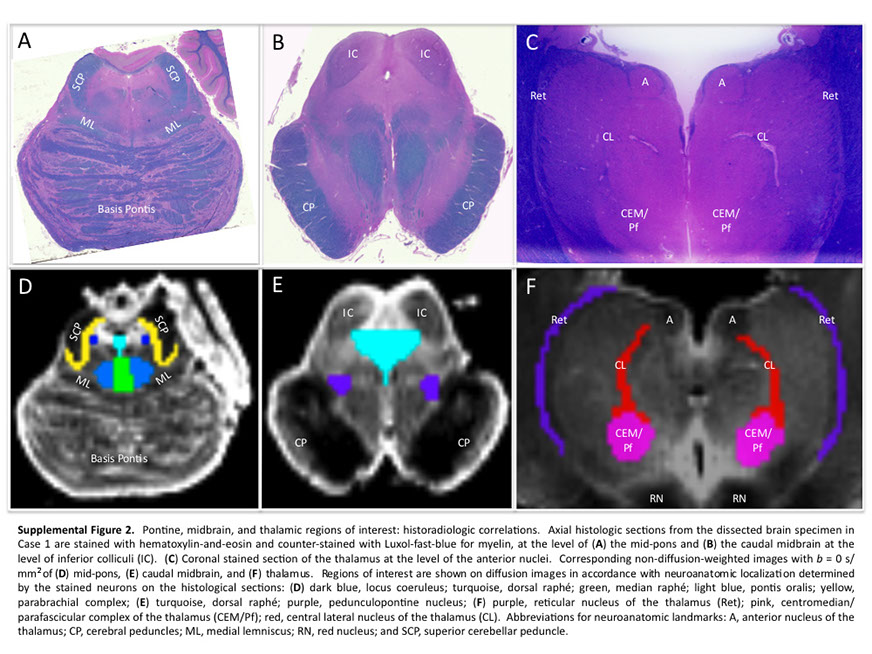

Many observations suggest that CFS could derive from residual damage to the reticular activating system (RAS) of the upper brain stem and/or to its cortical projections. It should be pointed out that although the larger right greater than left asymmetry in regional cerebral blood flow is found at the parietotempotal level in CFS patients as compared to healthy controls, no significant correlations are found between frontal tracer uptake and right-left parietotemporal asymmetry, on the one hand, and clinically relevant CFS dimensions on the other. Damage to the RAS could be produced by a previous viral infection, leaving functional defects unaccompanied by any gross histological changes.

In this respect, fluorine-deoxyglucose positron emission tomography showed specific metabolism abnormalities in CFS patients (hypometabolism in right mediofrontal cortex and brainstem) as compared with both healthy controls and depressed patients. The most relevant abnormality is brain stem hypometabolism, which has been also reported in single-photon emission computed tomography studies and seems to be a marker for the in vivo diagnosis of CFS